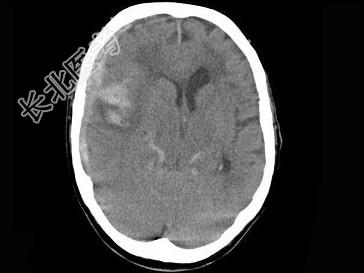

- 单项选择题女,79岁, 步行时突然摔倒,结合图像, 最可能的诊断是 ( )

A、右大脑中动脉破裂出血

B、脑转移瘤出血

C、脑膜炎

D、脑梗死

E、脑脓肿